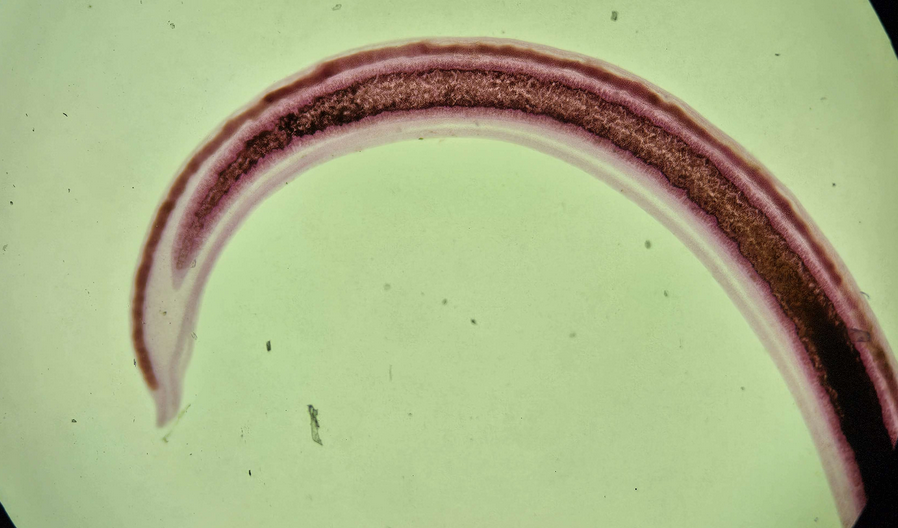

🪱🇯🇵 Schistosoma japonicum (Postać dojrzała)

😷❓ Parazytoza: Schistosomoza przewodu pokarmowego

🧩🦠 Organelle:

⚫️ - przyssawka gębowa;

🟡 - przyssawka brzuszna;

🔴 - rynienka.